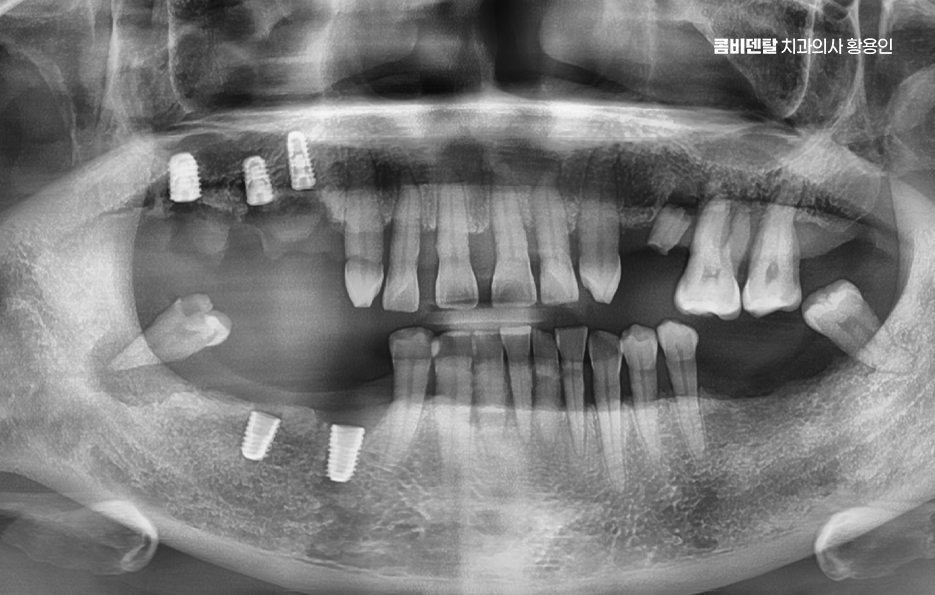

어금니 발치후 임플란트 안하면 먼저 생기는 문제는 치아 이동 현상으로 사람의 치아는 서로 의지하면서 균형을 맞추고 있는데, 어금니 하나가 빠지게 되면 그 자리를 메꾸기 위해 옆 치아들이 점점 쓰러지듯이 기울어지며 또 위아래 맞물리던 치아는 상대 치아가 사라지면 아래로 내려오거나 위로 솟구치면서 위치가 틀어질 수 있어요

결국 전체 치열이 뒤틀리고 교합이 망가지게 되는 것인데 이건 단순한 배열 문제가 아니라, 턱관절까지 영향을 줄 수 있는 변화로 이어지는 거예요.

그리고 사실 골 흡수의 문제가 무척이나 큰데 즉 잇몸뼈가 점점 사라지는 현상으로 치아가 뿌리로 잇몸뼈에 자극을 주고 있어야 뼈가 유지되는데, 치아가 빠진 상태로 계속 방치되면 그 부위 뼈는 서서히 꺼지듯이 흡수되기 시작하는 거예요.

이게 심해지면 나중에 임플란트를 하고 싶어도 뼈가 부족해서 뼈이식까지 같이 해야 하고, 수술 범위도 커지는 것이며 임플란트를 하지 않고 방치한 시간이 길수록 치료가 까다로워지고, 비용도 더 많이 들어가는 문제가 발생될 수 있었어요

나에게 맞는 치료를 하기 위해서는 정확한 진단과 설계가 중요하며 CT 촬영 등을 통해 신경 위치, 뼈의 양, 두께 등을 정밀하게 진단한 다음, 교합과 치열 구조에 맞는 위치에 임플란트를 심는 게 중요한데 잘못된 위치에 심어지면 오래 쓰기 어렵고, 나중에 통증이나 염증이 생길 수 있었어요.